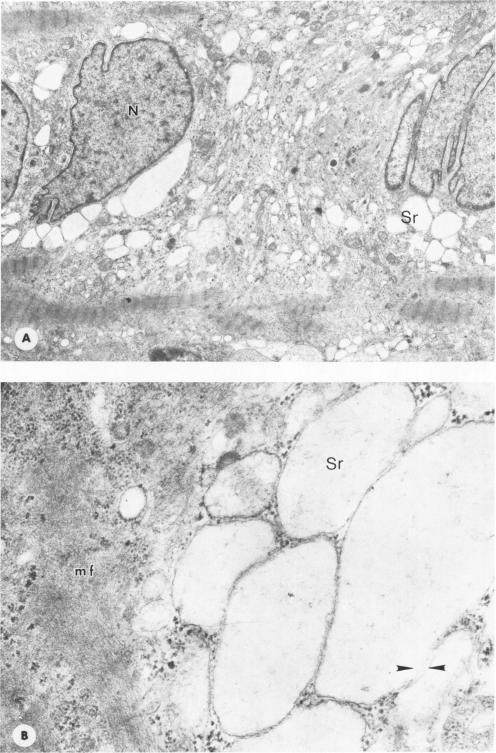

Skeletal muscle samples from the upper and lower extremities of 38 human fetuses (6 to 18 weeks' gestation) of both sexes were studied by histologic, histochemical, and electron microscopic methods. Ultrastructural morphometry was applied. In the different stages of normal development are found regressive changes, ranging from reversible dystrophic to irreversible necrotic alterations, which are characteristic of either primary myogenic myopathies or primary neurogenic muscle atrophies in older age. Several pathologic patterns of so-called congenital myopathies also presented. On the basis of their findings, the authors conclude that in a certain group of congenital myopathies full normal development of muscle is hindered or blocked and that groups of muscles or the whole voluntary musculature is arrested at certain stages of maturation. For example, insufficient or absent innervation of the fetal muscle may be a factor in Werdnig-Hoffmann or Kugelberg-Welander syndromes. The authors' findings suggest that pathologic patterns in muscle diseases have been used physiologically in fetal development to eliminate unnecessary overproduction of muscle fibers.

采用组织学、组织化学和电子显微镜方法,对38例不同性别的人类胎儿(妊娠6至18周)上下肢的骨骼肌样本进行了研究。应用了超微结构形态测量法。在正常发育的不同阶段发现了退行性变化,范围从可逆性营养不良到不可逆性坏死改变,这些变化是老年原发性肌源性肌病或原发性神经源性肌肉萎缩的特征。还呈现出几种所谓先天性肌病的病理模式。基于他们的发现,作者得出结论,在某一组先天性肌病中,肌肉的完全正常发育受到阻碍或阻断,并且肌肉群或整个随意肌在成熟的某些阶段停滞。例如,胎儿肌肉的神经支配不足或缺乏可能是韦尔纳格 - 霍夫曼或库格尔贝格 - 韦兰德综合征的一个因素。作者的发现表明,肌肉疾病中的病理模式在胎儿发育过程中已被生理利用,以消除不必要的肌纤维过度产生。